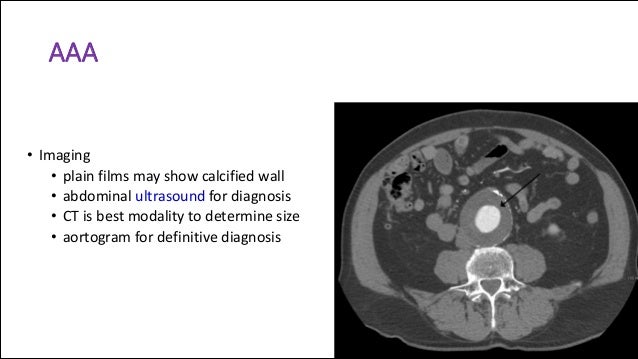

Pain can arise from the colon, urinary tract, reproductive organs, vascular a ruptured abdominal aortic aneurysm can result in sudden pain radiating to the left lower abdomen and back. I've had a transvaginal ultrasound showed nothing, blood and urine are clear, i have irregular very heavy with a lot of clotting. I don't feel sick but this pain is really constant now.